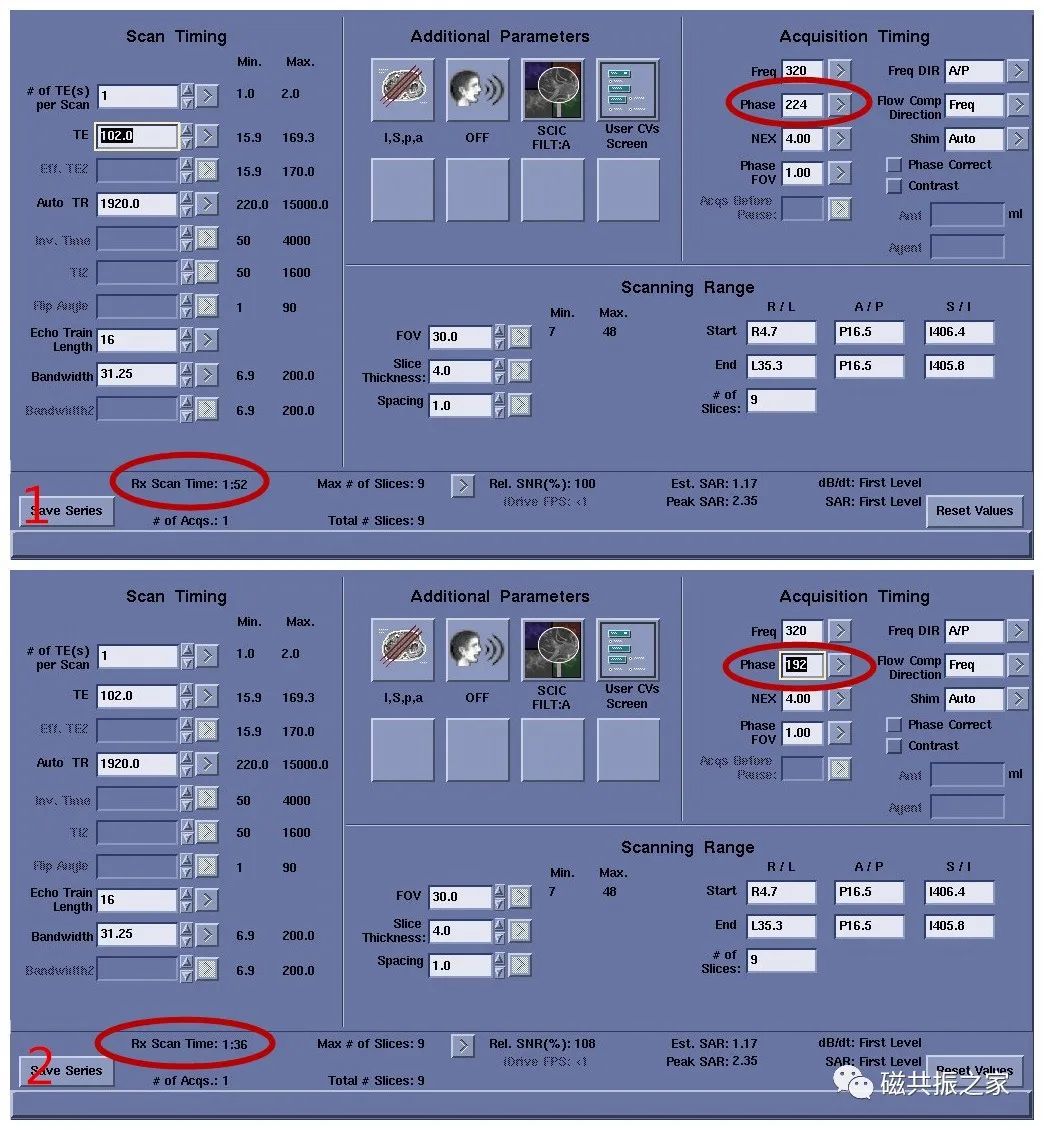

相位编码

图1,Phase为224时,扫描时间为1:52,图2,Phase为192时,扫描时间为1:36。虽然相对信噪比由图1的100% 变了图2的108%,但会影响其图像分辨率。同时频率编码也会影响扫描时间。